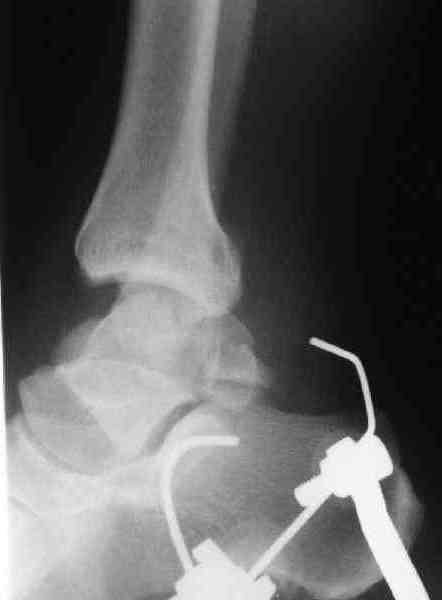

И второй случай из недавней ташкентской практики, (извините за качество ренгенограммы и только в одной проекции) случай падения с высоты (кстати моего друга - известного киноактера) - открытый

смещенный перелом тарана, с переломом переднего края дистального эпиметафиза большеберцовой кости.

При поступлении в приемной сделана первичная обработка с ушиванием открытой латеральной раны и вытяжением за пятку.

Из-за отсутствия времени пришлось оперировать на второе утро, из материала, что имеем на месте, фиксирован двумя шурупами, а третий-это контур сломанного жойстика в 4 мм. На дистальный медиальный конец тибиа antiglide 3.5 мм пластина. Через пару дней выписан и несмотря на предупреждение, самостоятельно начал нагрузку в 4 недели, время не ждет, снимается в боевике в Росийской Федерации.